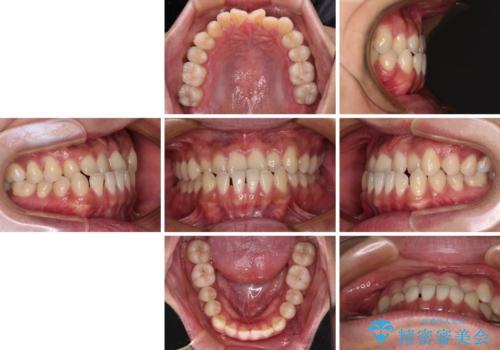

- 前歯のクロスバイトを気にして来院された患者様です。

1年半後に結婚式が控えているとのことで、ワイヤー矯正で早めに治療を終えることを希望されました。

骨格的に下顎が前方に位置していましたが、歯列矯正で改善できると判断し、ワイヤー装置にて矯正治療を行うこととしました。

骨格的な左右差も顕著であったため、正中は合わず、上下前歯の一部が接触しない咬み合わせとなることが予想されましたが、正中はもともとのズレが小さかったことから、合わせることができました。

治療期間も10か月間という短期間で終了し、患者様には大変満足していただきました。